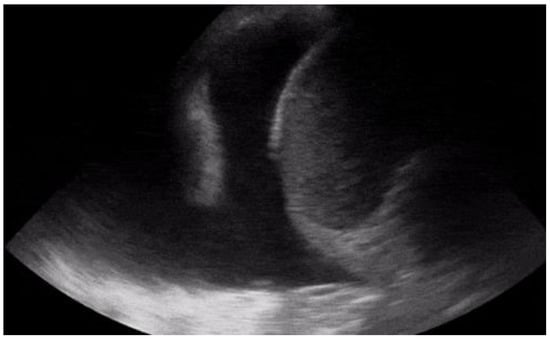

Another condition in which echocardiography can help the physician is the finding of hypoechoic material between the two layers of the pericardium, which allows us to make a diagnosis of pericardial effusion (Figure 1). Another advantage is that the ultrasound performed in the emergency room by the emergency doctor has a very high sensitivity (96%) and specificity (98%) towards this pathology [14].

Figure 1. POCUS echocardiography: subcostal projection with pericardial effusion.

Knowing how to identify a pericardial effusion also allows us to diagnose much more dangerous clinical pictures, such as cardiac tamponades [15].